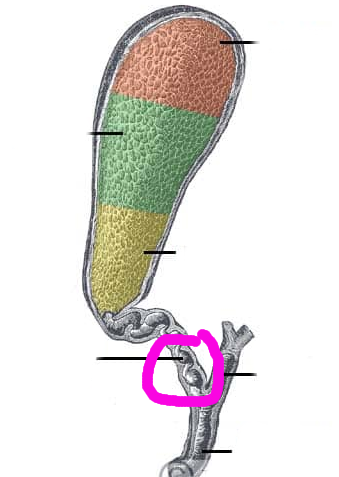

Fundus region

purple highlight

Cardia region

green highlight

Body of stomach

blue highlight

Pylorus of stomach

yellow + orange highlights

Cardiac orifice

Esophageal lumen

Pyloric sphincter

Pyloric orifice

Duodenum

blue highlight